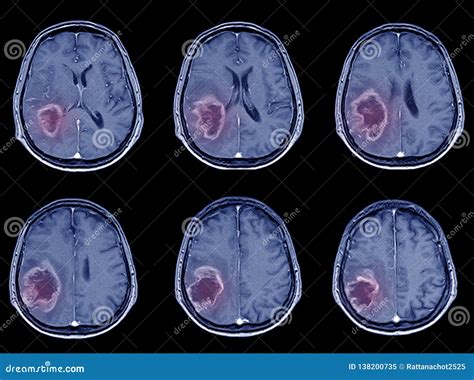

So, the CT scan is done, and now the radiologist and stroke team are huddled around the images. What exactly are they looking for? Well, in the very early stages of an ischemic stroke , the CT scan might actually look normal. That’s because it can take a few hours for the signs of damage to become visible. However, there are some subtle changes that experienced radiologists can spot. One of the earliest signs is called the “dense artery sign.” This refers to a bright spot on the CT scan that indicates a blood clot blocking an artery in the brain. Another early sign is the loss of gray-white matter differentiation. This means that the normal distinction between the gray matter (the outer layer of the brain) and the white matter (the inner layer) becomes blurred. As time passes, more obvious signs of ischemic stroke will appear on the CT scan . These include areas of hypodensity, which are dark patches that indicate brain tissue that has been damaged by the lack of blood flow. Doctors will also look for signs of swelling in the brain, which can be a complication of ischemic stroke . Importantly, they’re also looking to rule out any signs of bleeding, which would indicate a hemorrhagic stroke and change the course of treatment. So, in summary, radiologists are looking for a combination of subtle early signs and more obvious later signs to confirm the diagnosis of ischemic stroke , assess the extent of the damage, and rule out other conditions.